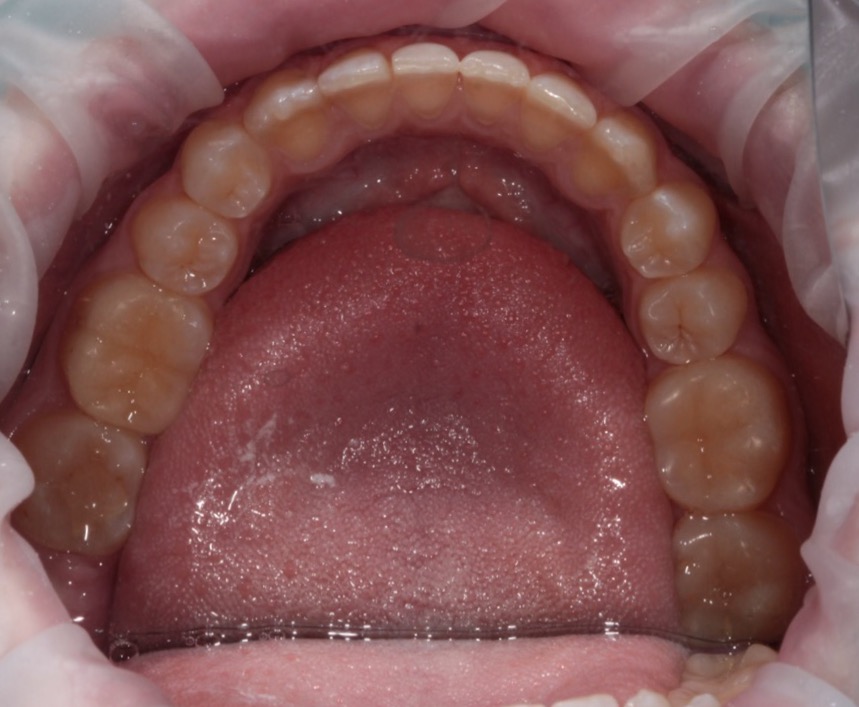

Invisalign состоит из набора индивидуальных, практически невидимых, съёмных капп(элайнеров), сменяемых 1 раз в 2 недели. Элайнеры за этот срок перемещают зубы до рассчитанного положения, после чего пациент меняет их на следующую пару.

Каппы сделаны из специального прозрачного материала, благодаря свойствам которого они плотно прилегают к зубам и совершенно невидимы при разговоре, улыбке и даже на фотографиях.